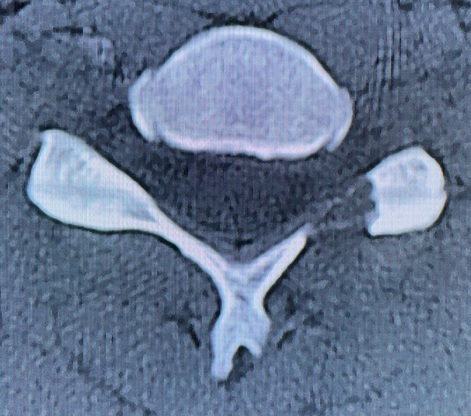

BKP(経皮的椎体形成術)

日本は世界中の国のなかで最も高齢化が進んでおります。そのため骨粗鬆症(骨がもろくなる病気)の患者様の割合も年々高くなっております。

骨粗鬆症になってしまうと体の様々な部位の骨折をしやすくなってしまいます。骨折を起こしやすい部位のなかで脊椎(せぼね)の骨折があります。

転んで骨折することもありますが、「いつのまにか骨折」という明らかなきっかけがわからずに骨折を起こしてしまう患者様もおられます。

症状として寝返りをうつ時、起き上がる時などで背中や腰に痛みがでます。

せぼねの骨折を繰り返すと、「腰まがり」になって真っすぐ歩けなくなったり、「寝たきり」の原因になることもあります。脊椎圧迫骨折の治療として、従来は保存的治療としてコルセットを装着して骨折部位が自然と治るのを待つ方法が一般的でした。しかし、コルセットの固定力には限界もあり骨折椎体がつぶれたり、骨がくっつかない(偽関節といいます)こともあります。なかには、さらに進行して下肢の麻痺が出現してしまうことがあります。

2011年より脊椎圧迫骨折に対する椎体形成術(BKP)が保険適用となりました。BKPはBalloon Kyphoplastyの略称です。

脊椎圧迫骨折によってつぶれてしまった椎体(せぼね)を安定させ、早期に痛みを軽減することにより、骨折前の生活に戻りやすくすることができます。

全身麻酔が必要ですが、手術時間は約30分で、傷口は5㎜程度のものが2か所です。出血はほとんどありません。

お体に大きな問題がなければ手術の翌日から動き出すことができ、早い方では術後数日で退院も可能です。退院後は骨の状態を診るため定期健診を行います。脊椎圧迫骨折の手術と並行して骨粗鬆症の治療が必要になります。

骨折の折れ方、全身状態などによってはBKP治療の対象にならない場合もありますので、担当医にご相談ください。